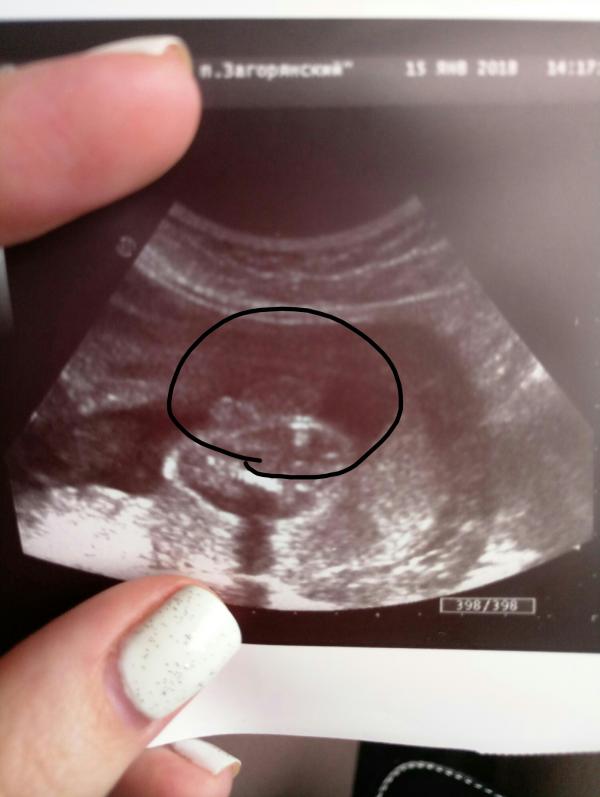

Сходила я на узи, срок 26 недель ровно. Всё хорошо, правда есть однократное обвитие. Конечно, так крутиться у мамы в животе… Позавчера вообще казалось, что поперёк улёгся и пихал в бока, одновременно в оба. Вес 870 грамм посчитали. Лежит вниз головой, головка прижата к шейке. Показали, как сосёт руку, но не кулак, а ниже кисти. А потом в позе рукалицо 😂 Собственно, я его понимаю. Мать то в расстроенных чувствах - третий мальчик… Не нравится ни одно имя, вообще. И я всё равно ещё надеюсь попасть в тот процент женщин, которым всю беременность на узи 100% говорят один пол ребёнка, а рождается другой 😆 Надежда умирает последней, пусть и фото причендалов имеется. 🙄